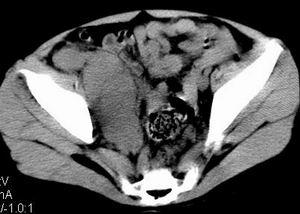

| 患者,男,9岁,因右下腹包块入院,血象不高,不规则发热,常超40度。 平扫: ![]() ![]() ![]() ![]() ![]() ![]() ![]() ![]() ![]() ![]() ![]() ![]() ![]() ![]() ![]() ![]() ![]() ![]() 增强: ![]() ![]() ![]() ![]() ![]() ![]() ![]() ![]() ![]() ![]() ![]() ![]() ![]() ![]() jiajie发言:骶椎右前区不规则软组织肿块,边缘光整,密度均匀,增强后均匀强化,右腹股沟区可见肿大淋巴结,临床有时发热,考虑淋巴瘤,儿童盆腔肿瘤应与神经母细胞瘤和横纹肌肉瘤鉴别。 longzhanghui发言:印象:盆腔右后壁不规则软组织肿块,并向前延伸.似为多个肿块融合,呈中等强化.初步考虑淋巴瘤. 听蝉观竹发言:右侧髂内、外组淋巴结肿大,从其形态和融合的情况看,同意大家意见-----考虑恶性病变,但是9岁男孩还要注意检查睾丸情况,有无隐睾? 常常类似情况是隐睾发生精原细胞瘤淋巴结转移,这个病例也要注意这一点!!! 广东凌发言:大家好,在这里我想说一下个人观点,我建议上传图片的同志能否辛苦一点就是把病史和图片都上传完整一点,比如这个病人的腹膜窗,并且这个病人的肠道的准备也是不怎么好,就从现有的质料看:病灶属于淋巴结肿大当无大的争议,有融合趋势,其内无坏死,边缘强化为主,故考虑:淋巴瘤!建议用腹膜窗看一下和肠道的关系! 阿圣发言:病灶属于淋巴结肿大当无大的争议,有融合趋势,其内无坏死,边缘强化为主,故考虑:淋巴瘤 结果是:淋巴瘤 病例来源:ct762。由宁静致远发布: http://www.radinet.com.cn/forum_view.asp?forum_id=4&view_id=2182 |